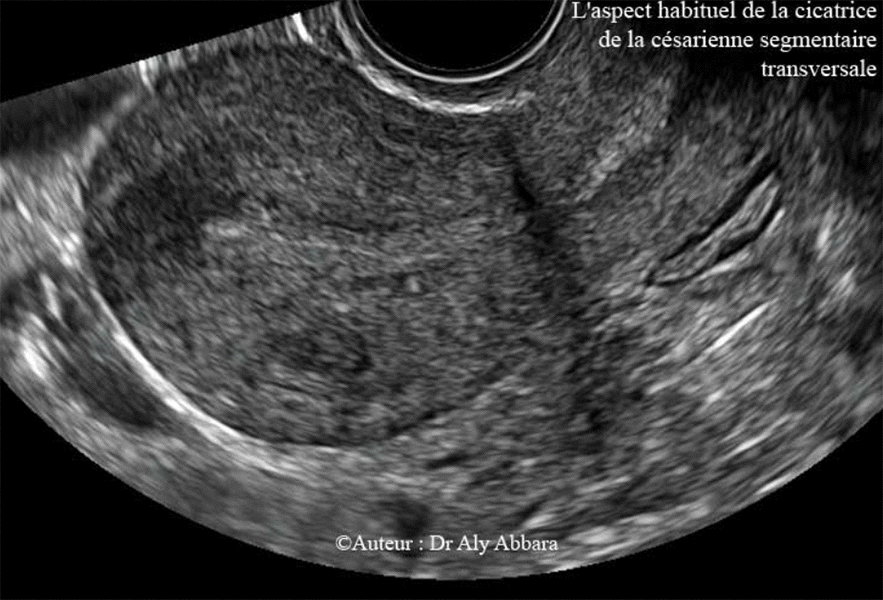

Utérus cicatriciel - L'aspect habituel de la cicatrice de la césarienne segmentaire transversal

• Coupe sagittale de l'utérus - voie endovaginale.

• L'aspect échographique habituel (par balayage de l'isthme utérin) de la cicatrice de la césarienne segmentaire transversale :

• Une bandelette irrégulière hypoéchogène plus ou moins linéaire, traversant verticalement la paroi antérieure de la région isthmique de l'utérus ; puis dans certaines incidences, on peut observer l'apparition d'une cône d'ombre derrière cette bandelette cicatricielle.